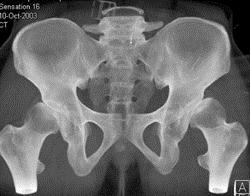

问题 男,23岁,行走跛行,外展受限,两下肢不等长,结合图像,最可能的诊断是 ( )

选项 A、先天性髋内翻 B、髋关节结核 C、髋关节后脱位 D、髋关节前脱位 E、髋关节中心脱位

答案 C